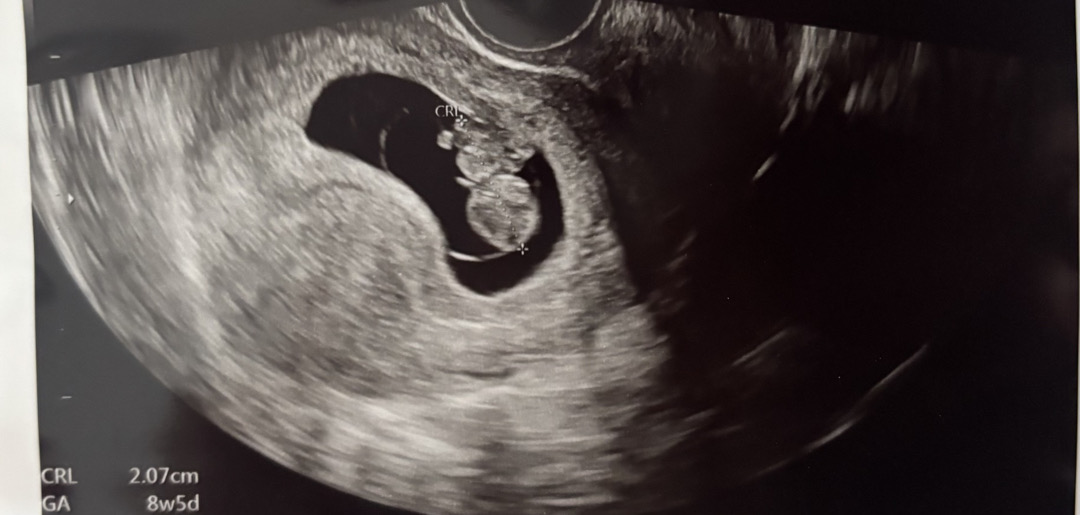

저도 10주차입니다!! 8주에 병원가서 젤리곰보고 4주후인 12주 예약인데 아직 2주나 남았네.... 입덧 할때면 잘 있구나~~? 하다가 좀 덜해지면 불안 하긴 하지만 첫째때는 입덧 없었어도 잘 자라줬기에 둘째도 믿어보려구요! 2주뒤에 가면 혹시나~~ 성별을 알 수 있으려나~~~? 기대하며 시간을 보냅니다ㅎㅎ